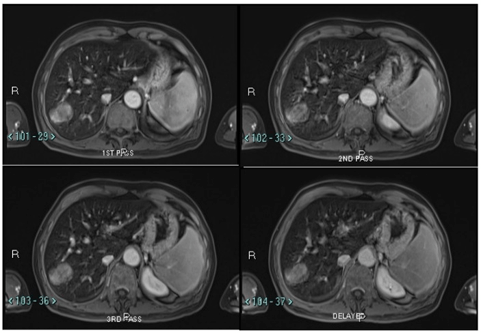

Figure 3A: Non-contrast fat saturated T1 magnetic resonance imaging of the liver with diffuse low signal of hepatic parenchyma from iron deposition. The lesion in segment VII is minimally T1 high signal.

Figure 3B: Magnetic resonance imaging of the liver that shows lobulated mass in segment VII, with mild heterogenous contrast enhancement without significant enhancement in the arterial phase or washout or pseudo capsule on portal venous or delayed phases.

We proceeded with a computed tomography of the liver (CT liver) for further evaluation. CT liver showed a 4.3 x 2.4cm heterogeneously hypodense lobulated mass in segment VII of the liver. The mass was hypodense to the liver on all phases (plain, arterial, venous and delayed). There was mild heterogeneous enhancement, but there was no arterial enhancement (Figure 2A), washout (Figures 2B & 2C) or pseudo capsule, which should be expected in hepatocellular carcinoma. In view of the known history of thalassemia and the presence of paravertebral soft tissue masses that were likely to be extramedullary haematopoiesis, the possibility of extramedullary haematopoiesis was suggested. The other lesion was a 0.9cm hypodensity in segment VI of the liver, which was diagnosed as a flash-filling haemangioma. A magnetic resonance imaging (MRI) was then ordered for the indeterminate segment VII lesion. On MRI, the hepatic segment VII mass in question showed mild heterogeneous contrast enhancement but no appreciable arterial enhancement, washout or pseudo capsule (Figure 3A & Figure 3B).

The lesion remained indeterminate due to the absence of typical features for hepatocellular carcinoma. Extramedullary haematopoiesis remained a possibility and a tc-99m sulphur-colloid scan was suggested for further characterisation. On MRI, the liver also showed marked low signal on T1 and T2 as well a gain in signal on the in-phase T1 scan. These findings were compatible with hepatic hemosiderosis. MRI also confirmed that the smaller lesion in segment VI was a flash-filling haemangioma.